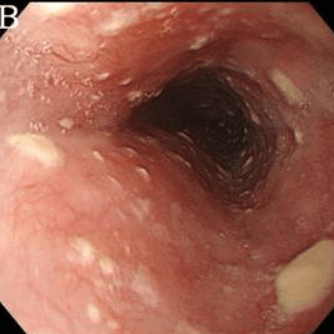

Эндоскопические признаки кандидоза пищевода — гиперемия и контактная ранимость слизистой оболочки, а также фибринозные налеты различной локализации, конфигурации и размеров. Среди всего разнообразия визуальных признаков кандидоза пищевода можно выделить три группы типичных изменений:

Катаральный эзофагит. Наблюдают диффузную гиперемию различной степени (от слабовыраженной до яркой) и умеренный отек слизистой оболочки. Характерным эндоскопическим признаком является контактная кровоточивость слизистой оболочки, иногда — с образованием нежного, белесоватого («паутинообразного») налета на слизистой оболочке. Эрозивных изменений не отмечают.

Фибринозный (псевдомембранозный) эзофагит. Наблюдают бело-серые или бело-желтые рыхлые налеты в виде округлых бляшек диаметром от 1 до 5 мм, выступающие над ярко гиперемированной и отечной слизистой оболочкой. Контактная ранимость и гиперемия слизистой оболочки заметно выражены.

- Катаральный эзофагит. Характеризуется гиперемией слизистой пищевода и умеренной отечностью. На кандидозную инфекцию указывает тонкий паутинообразный налет на эпителии, контактная кровоточивость.

- Фибринозный эзофагит. В пищеводе образуются беловато-серые налеты в виде бляшек размером до 0,5 см. Гиперемия, отечность и кровоточивость слизистой оболочки выражены интенсивнее, чем при катаральной форме.

- · Диагноз кандидозного эзофагита устанавливается, как правило, при эзофагоскопии, когда выявляются белые и белесовато-желтые бляшки и бляшкоподобные налеты на слизистой оболочке пищевода. Зачастую участки белесоватого налета носят диффузный характер, и покрывают всю поверхность слизистой оболочки пищевода.

- · Патогномоничным признаком кандидозного эзофагита является тот факт, что налет с трудом снимается биопсийными щипцами и после его удаления остаются участки осаднения слизистой оболочки.

Степень I: Несколько приподнятых белесоватых бляшек размерами до 2 мм в диаметре, с гиперемией, но без отека или язв.

Степень II: Множественные приподнятые белесоватые бляшки размерами более чем 2 мм в диаметре с гиперемией вокруг, но без отека или язв

Степень III: Сливные линейные и узловатые приподнятые бляшки, с гиперемией и язвами

Степень IV: Те же изменения, что и при III степени, плюс контактная кровоточивость слизистой оболочки и иногда сужение просвета пищевода